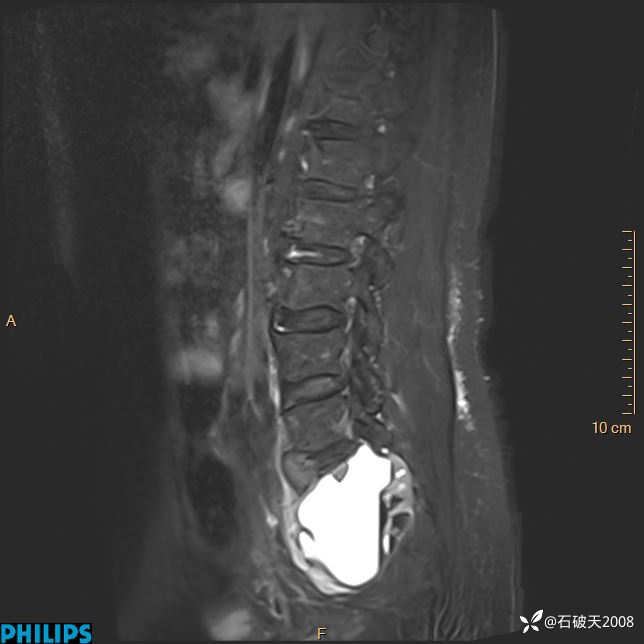

2023年3月份MRI影像

T1矢状位